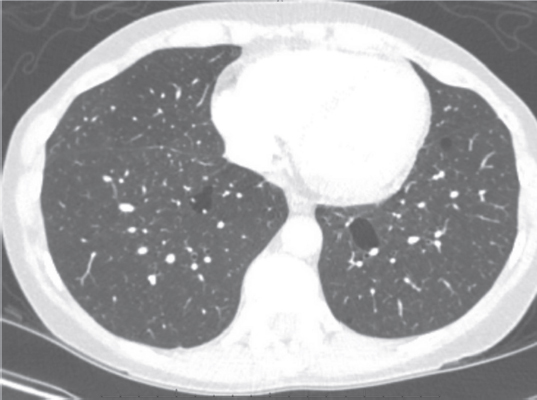

Laboratory studies included hemoglobin 12.9 g/dL, serum creatinine 0.70 mg/dL, NT-pro BNP 147 pg/ml, and TSH 0.92 mIU/L. ECG was significant for normal sinus rhythm. Prior cardiac stress test was negative for inducible wall abnormality. A pulmonary function test revealed normal spirometry and lung volumes. Computed tomography of the thorax with contrast (Figure 2) demonstrated cystic lesions of various sizes in both lung fields.

Figure 2

Figure 2. Computed tomography of thorax with contrast demonstrates cystic lesions of various sizes noted in both lung fields.